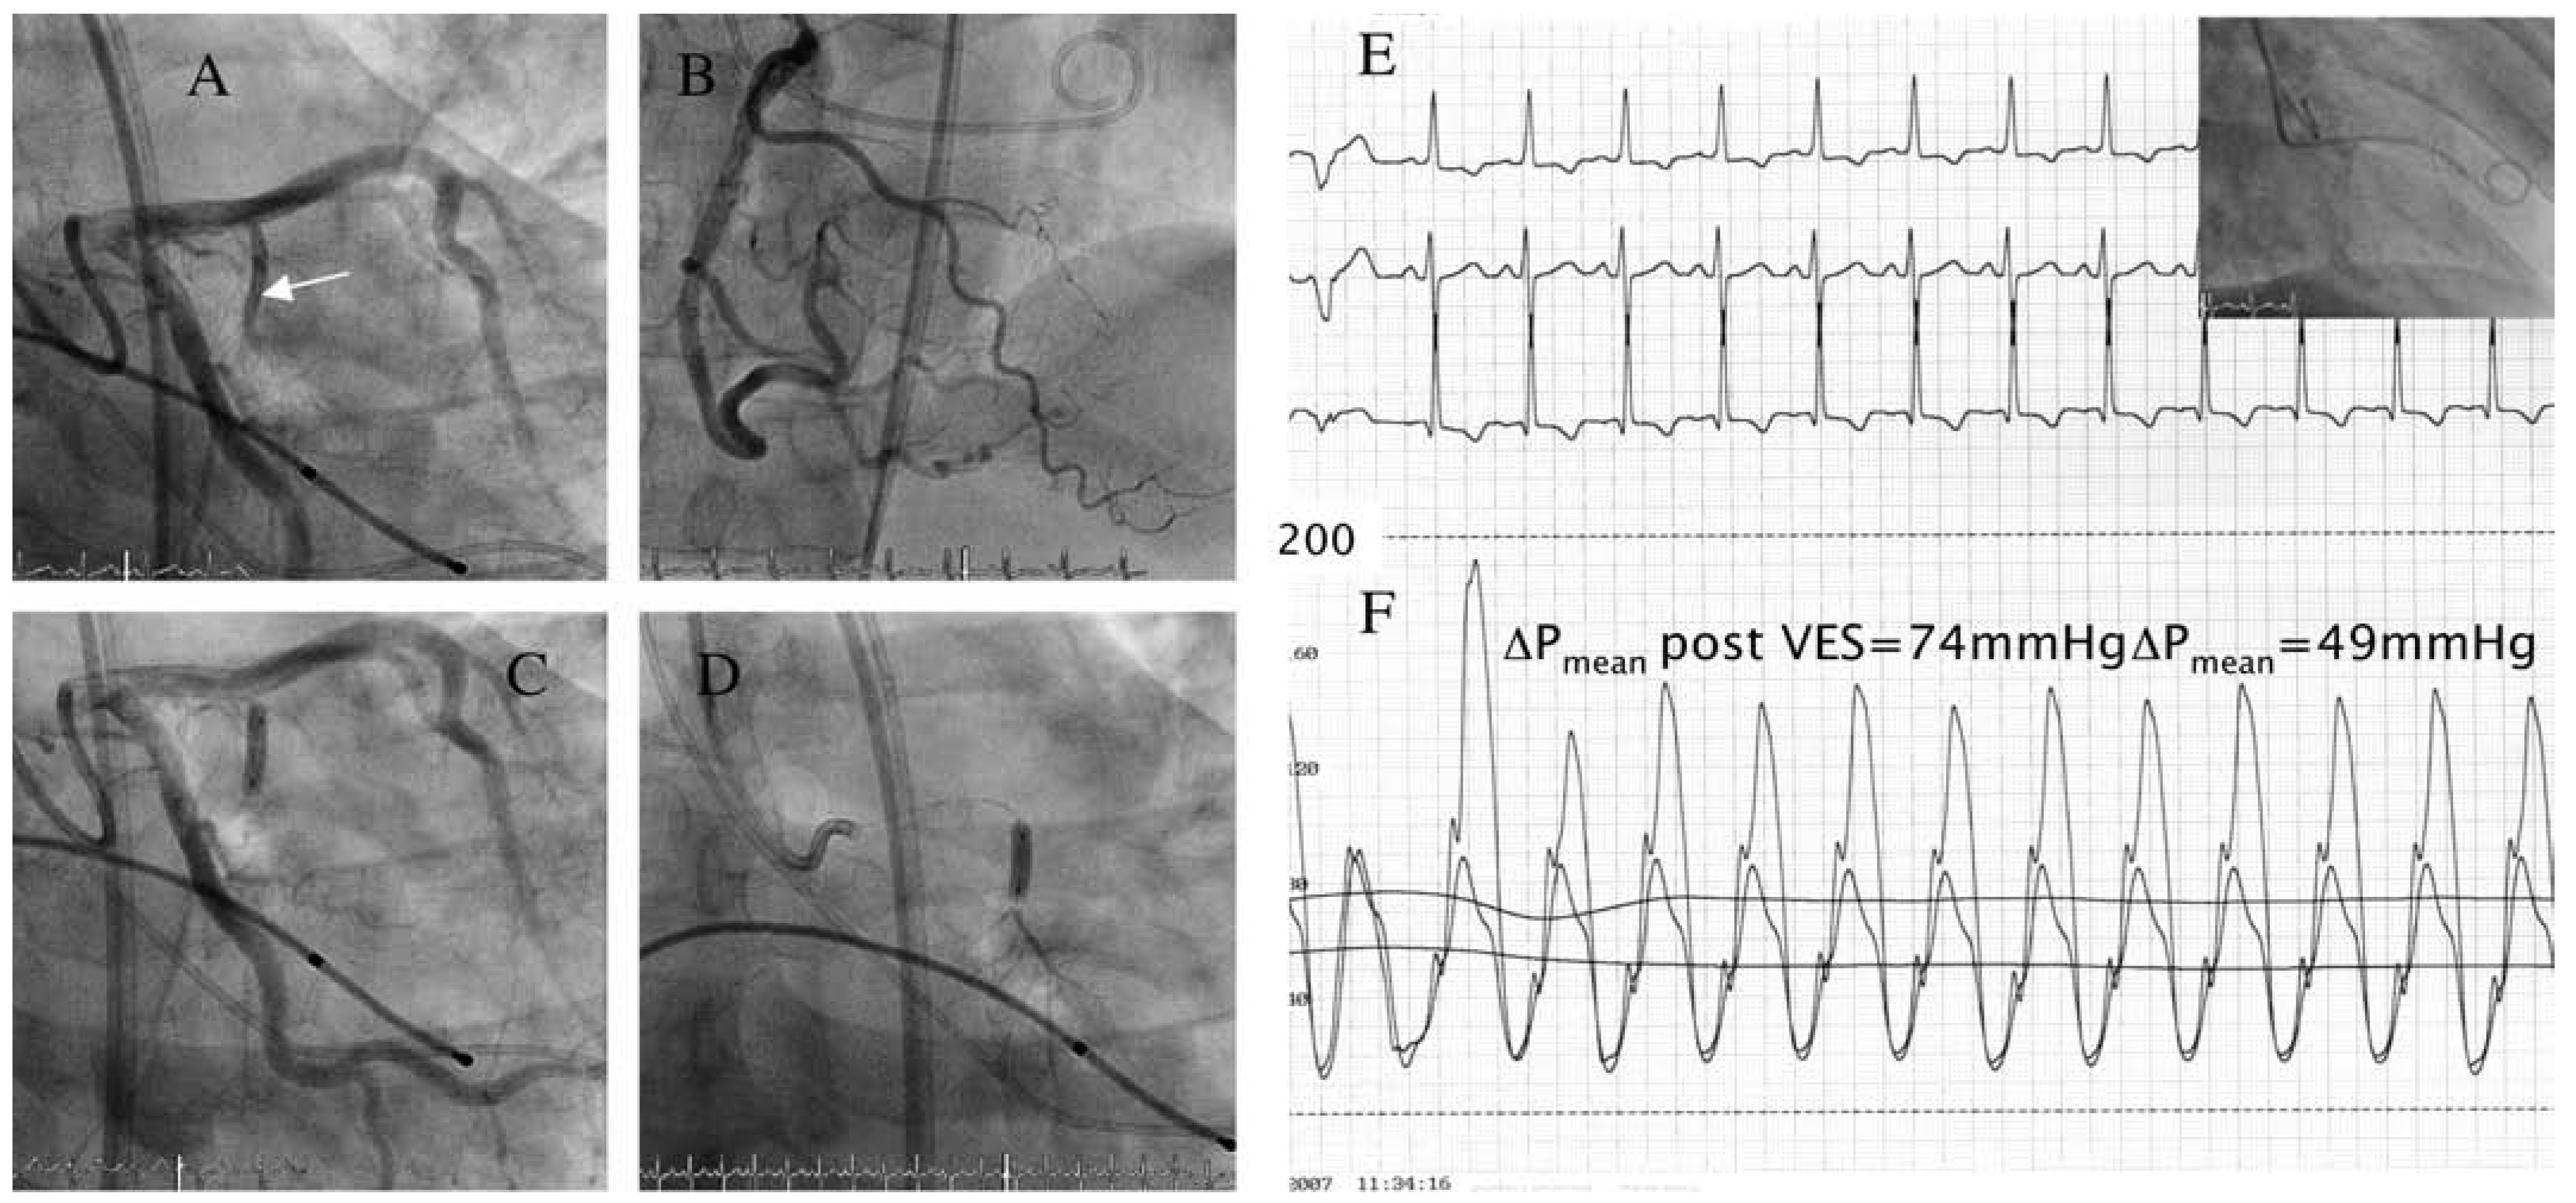

Transcoronary Ablation of Septal Hypertrophy in HOCM: Septal Collaterals May Cause Unwanted Inferior Myocardial Infarction

Case report